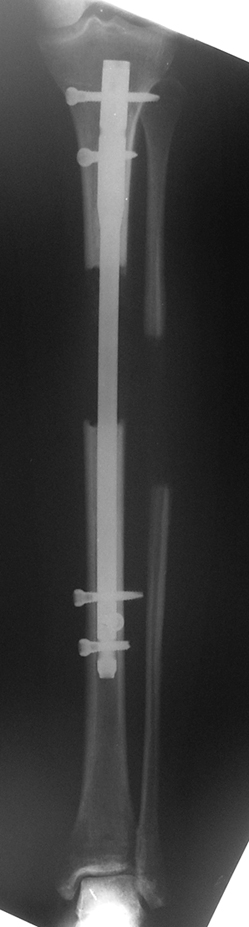

İntramedüller çivinin yerleştirilmesi ve osteotomi: Hasta traksiyon masasına supin pozisyonda yatırılır ve sağlam bacak altta olacak şekilde bacaklar makas pozisyonuna alınır. Standart yolla piriformis çukurundan medulla içine girilir ve kılavuz tel üzerinden kullanılacak çividen 1.5 mm daha kalın oyucu ile medulla oyulur. Proksimal femur, çivinin proksimali daha kalın olduğu için daha kalın oyulur. Radyografide osteotomi hattı planlaması yapılır. Planlama yapılırken uzatma sonunda distalde en az 8 cm. çivi kalması stabilizasyon için gereklidir. Kortikotomi perkütan olarak kortikotom ile tamamlanır. Daha sonra kılavuz tel çivinin boyunu ölçmek için distale ilerletilir. Uygun boyda intramedüller çivi çakılır. Son olarak çivi proksimalden kilitlenir ve bir adet dren konarak ameliyatın birinci kısmı tamamlanır.

Eksternal fiksatör uygulanımı: İntramedüller çiviye değmeden aşağıya ve yukarıya üçer adet Schanz vidası gönderilir. Vidalarla çivi arasında en az 1 mm den fazla mesafe olmalıdır.

Biz son zamanlarda, seçilmiş vakalarda, uzatma sonrası uzunluğu ve “alignment’ı” korumak amacı ile unilateral dinamik aksiyel fiksatör ve kilitli intramedüller çivi kombinasyonunu tercih etmekteyiz. Bu yöntemin ön şartları medullanın en dar çapının 7 mm.’den geniş olması ve uzatma sonrası distalde en az 8 cm. uzunluğunda çivi kalabilmesidir. İntramedüller çivi hem uzatma esnasında femurun üzerine gelen makaslama ve bükülme kuvvetlerini nötralize etmekte hem eksternal fiksasyon süresini kısaltmakta, hem de yeni oluşan kemiği kırıklara karşı korumaktadır. Serimizde bir vakada subtrokanterik femoral osteotomi yapılmıştır. İntramedüller çiviye rağmen varus angulasyonu oluşması yönünde bir dezavantaj tespit etmedik.

İlizarov, distraksiyon osteogenezisi için endosteal kan dolaşımının önemini vurgulamıştır. Biz tüm vakalarımızda femuru oyarak intramedüller çiviyi çaktık; buna rağmen hiçbir vakada kallus oluşma süresi tahminimizden daha uzun olmadı. Bu yüzden medüller dolaşımın bozulmasına bağlı yeni kemik oluşma hızında bir yavaşlama olmadığını düşünüyoruz. Oyma sonrası meydana gelen revaskülarizasyon, intramedüller çivili fiksasyon stabilitesi ve erken fonksiyonel yüklenme bu gerçeğin temelini oluşturmaktadır. Eksternal ve internal fiksasyon yöntemlerinin kombine kullanımının potansiyel dezavantajları kan kaybının artması, intramedüller infeksiyon, yağ embolisi olasılığı ve aşırı metal yüküdür. Bunların içinde en çok korkulan problem bir çivi dibi infeksiyonun tetikleyeceği derin intramedüller infeksiyondur (panosteomyelit). Bizim serimizde bu yönde hiçbir komplikasyon gelişmemiştir. Bu olası komplikasyonun önlenmesi amacı ile uzatma sonundaki kilitleme medialden yapılmalıdır; ayrıca intramedüller çivi ve eksternal fiksasyon pinlerinin teması önlenmelidir.